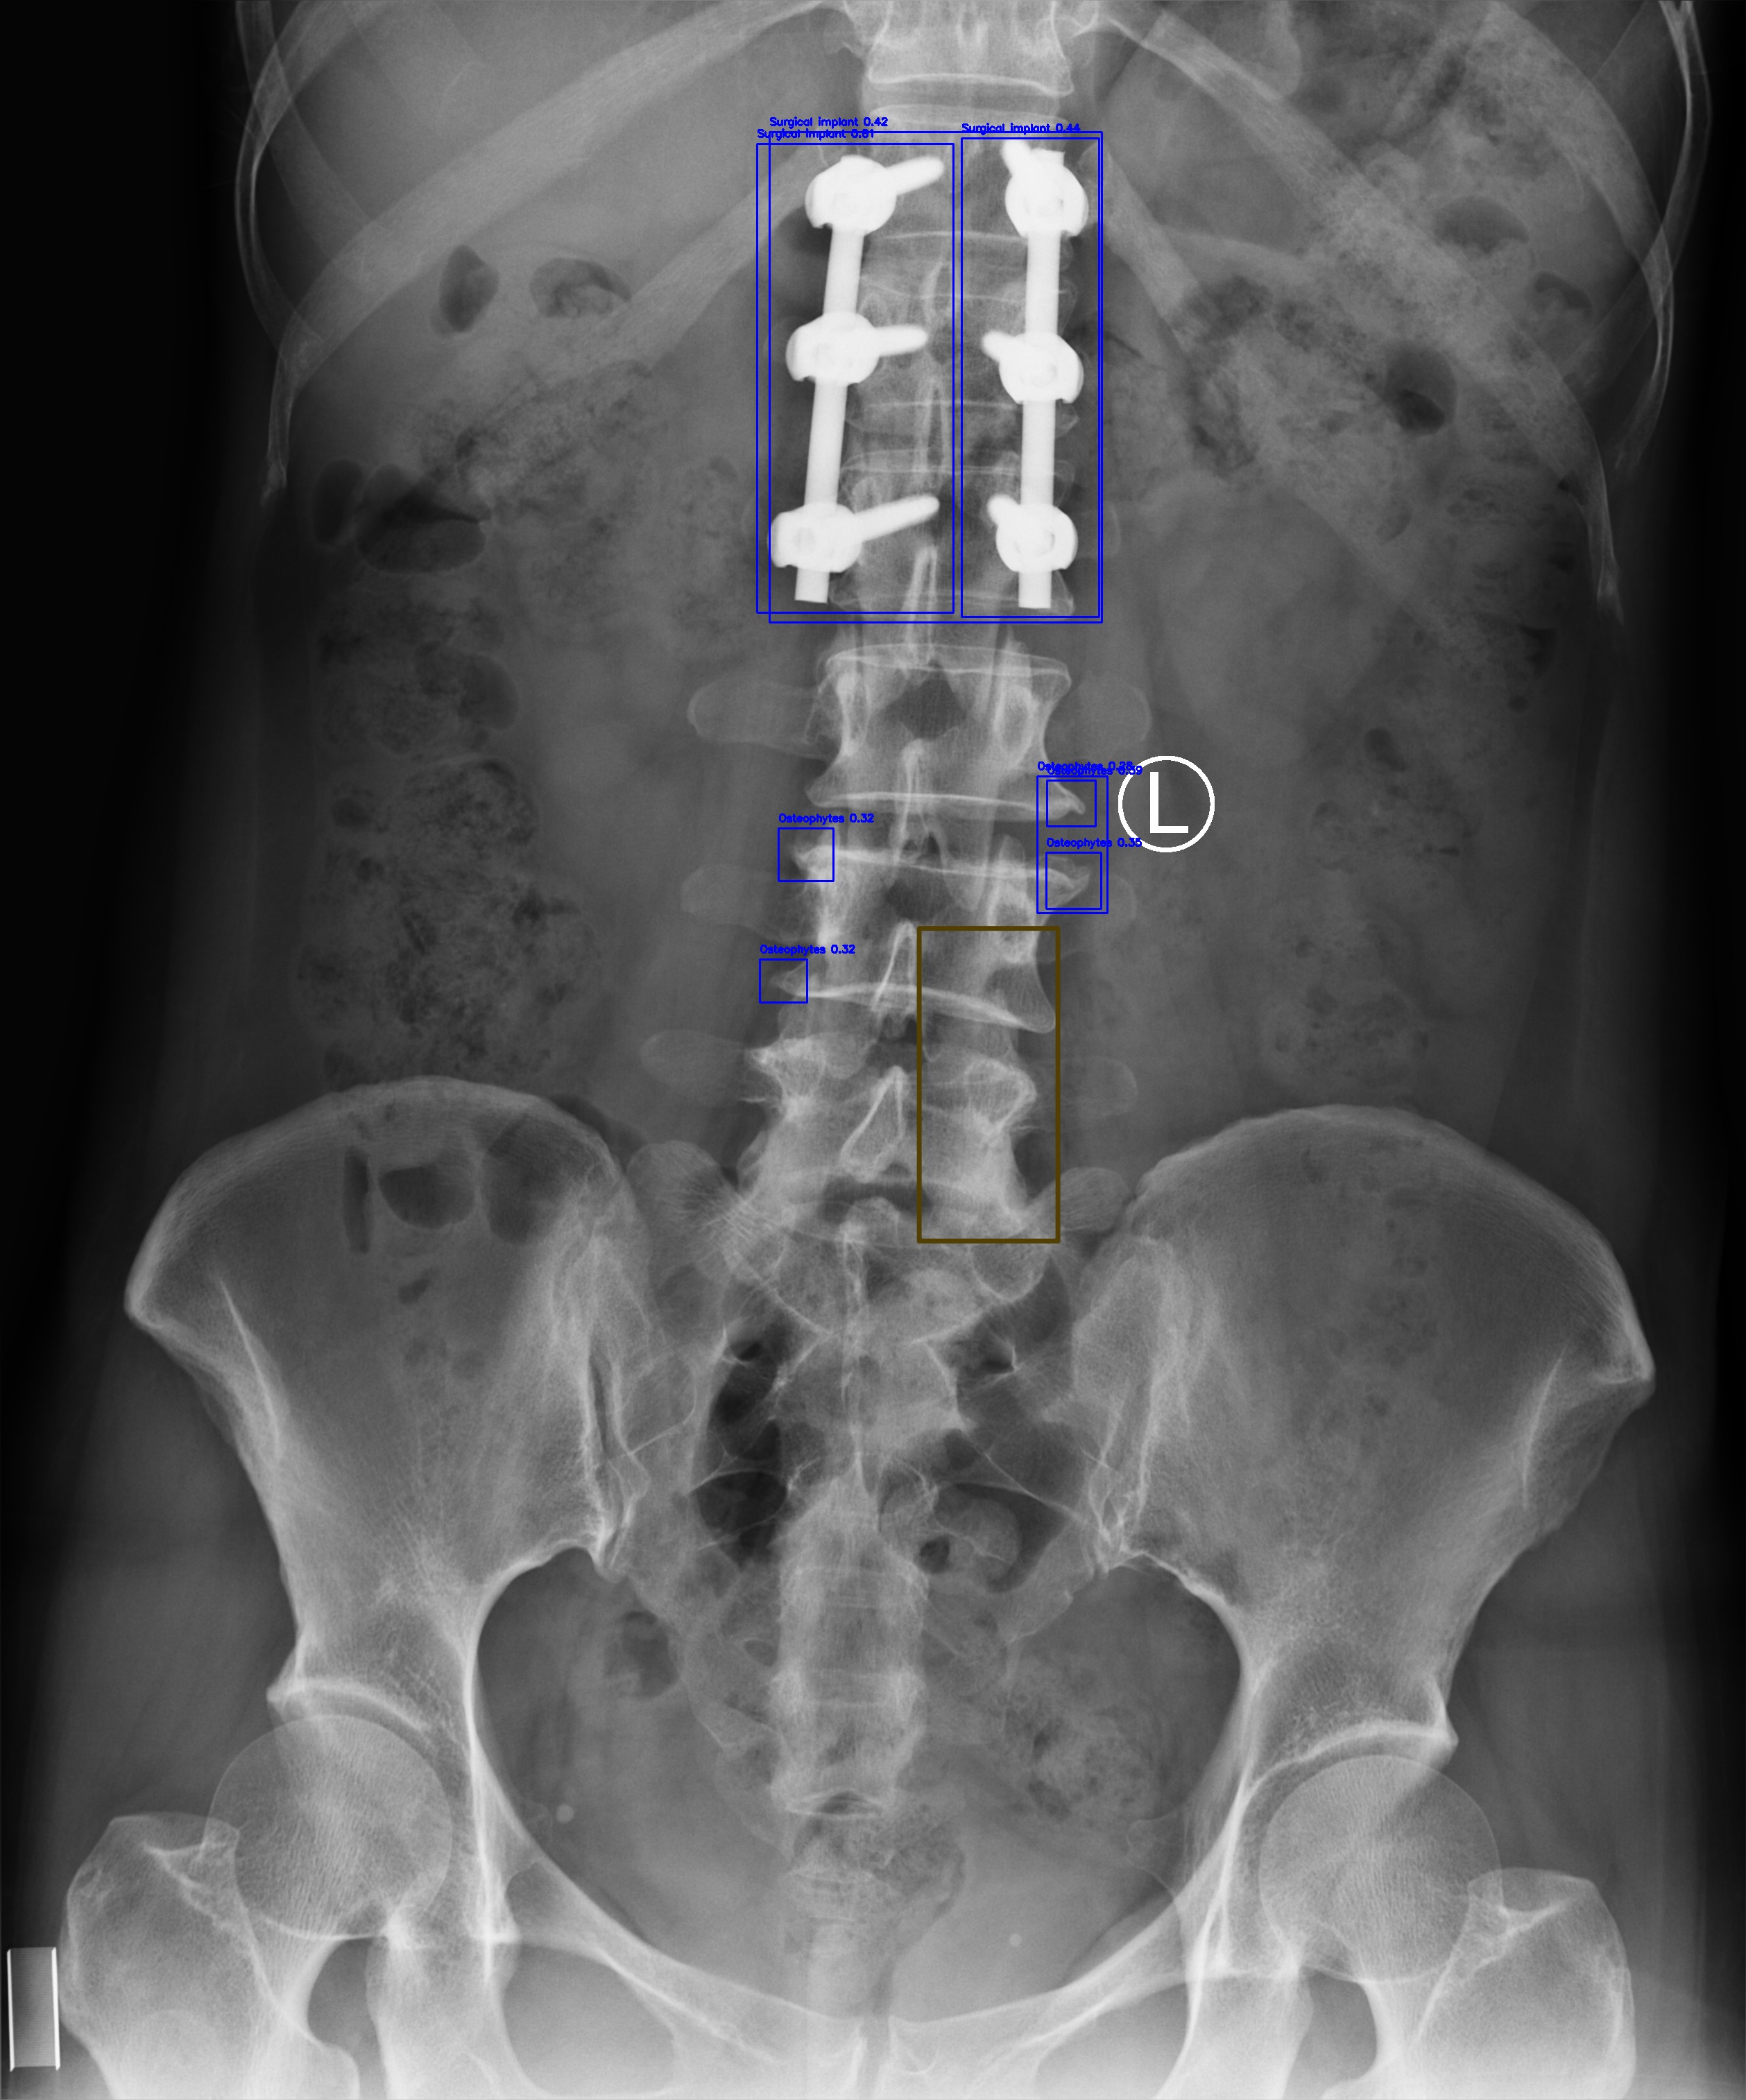

Surgical Implant

(d) Surgical Implant

Automated Lesion Detection and Localization: Visual demonstration of the cascaded DERNet-YOLO11 framework on VinDr-SpineXR benchmark images. The figure presents eight representative cases including seven pathological conditions with precise bounding-box localization: (a) Vertebral Collapse, (b) Osteophytes, (c) Spondylolisthesis, (d) Surgical Implants, (e) Disc Space Narrowing, (f) Foraminal Stenosis, (g) Other Lesions, alongside (h) a Normal spine radiograph for comparison. Each pathological case demonstrates the model's capability to accurately detect and spatially localize subtle lesions despite significant class imbalance (46.9:1 ratio), small object scales (often <1% of image area), and anatomical structure overlap. The localization boxes validate the clinical applicability of the integrated triage–localization pipeline.